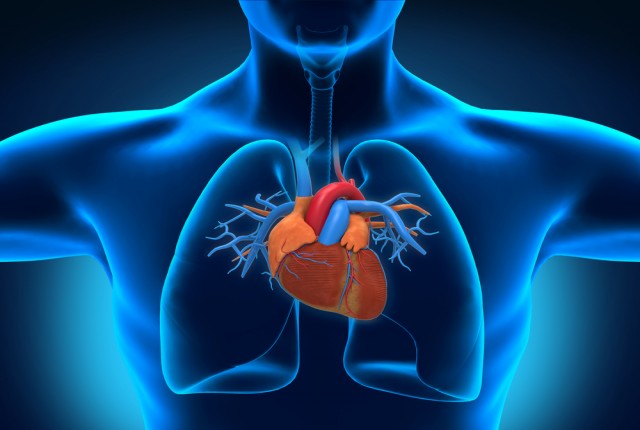

Οι καρδιές πολλών ανθρώπων γερνούν πιο γρήγορα απ’ ό,τι το υπόλοιπο σώμα – και εκτός από τον τρόπο ζωής, ρόλο παίζει και το επάγγελμα, σύμφωνα με μία νέα βρετανική έρευνα.

Η παγκόσμια εταιρεία υγείας Bupa δημοσίευσε τα ευρήματα από τις απαντήσεις που έδωσαν 8.000 καταναλωτές σε ένα online τεστ αξιολόγησης της ηλικίας της καρδιάς, το οποίο την υπολογίζει με βάση παραμέτρους όπως η χοληστερόλη, η πίεση, το οικογενειακό και ατομικό ιστορικό και διάφορες παράμετροι του τρόπου ζωής.

Το τεστ περιέχει επίσης ερωτήματα για την εργασία και τις ευκαιρίες για προσεγμένη διατροφή, άσκηση και καταπολέμηση του καπνίσματος και του στρες – δηλαδή για τους παράγοντες που είναι γνωστό ότι πλήττουν την καρδιά.